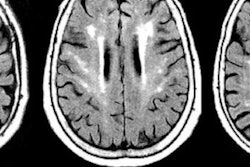

The government of Zimbabwe has commissioned the country's first diagnostic radiology and MRI center in Harare.